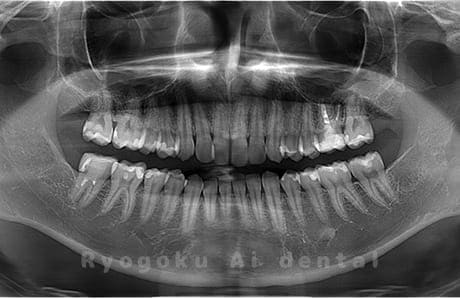

真っ直ぐ生えている親知らず

親知らずが真っ直ぐ生えているタイプです。

このタイプは真っ直ぐ生えていて咬み合わせに問題がなければ、抜歯しないケースもあります。ただし、虫歯になっていたり、痛みがあったり、咬み合わせが悪かったりすると抜歯をおすすめします。